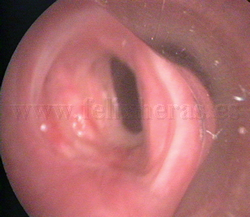

Estenosis

traqueal |